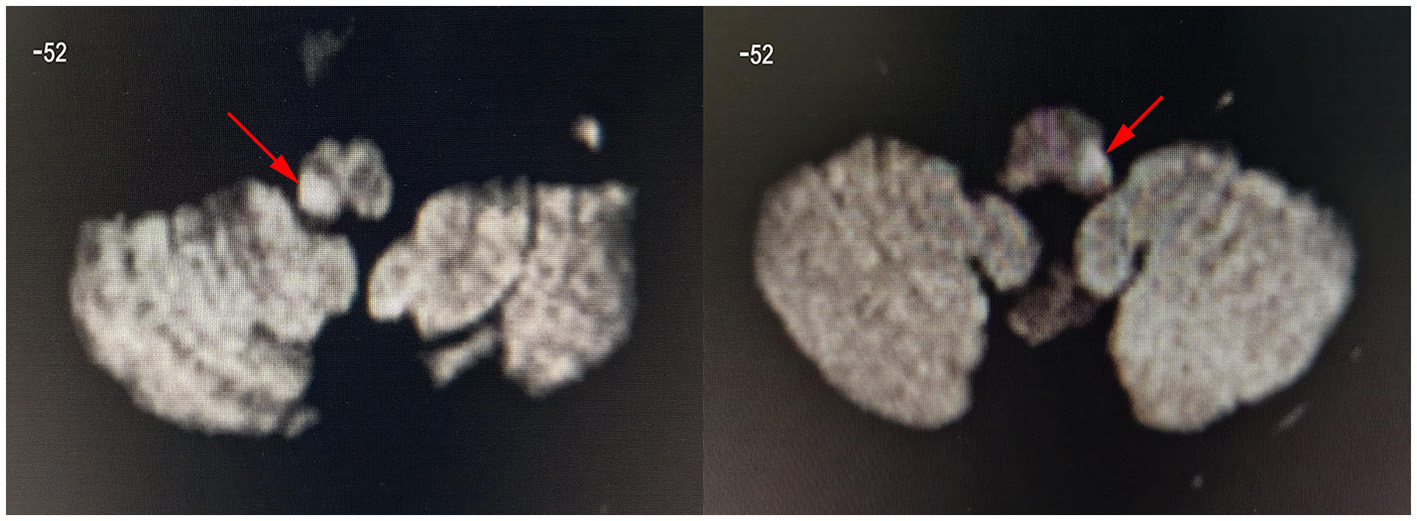

Figure 2

Diffusion-weighted images showing dorsolateral medulla infarction (arrow). These are the DWI images of patient 8 (left image, lesion located in the right medulla oblongata) and patient 1 (right image, lesion located in the left medulla oblongata). The z-value of the coordinate for the slice position is −52. All lesions were located in the left or right side of dorsolateral medulla oblongata.